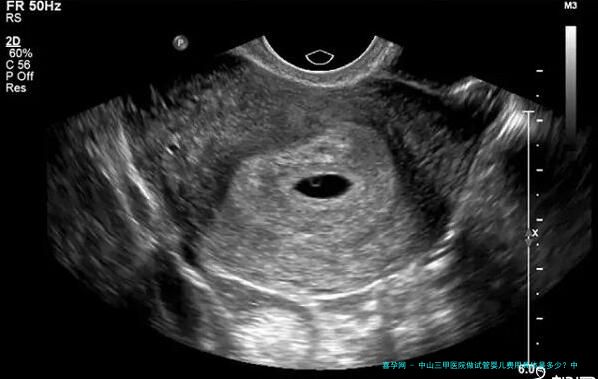

越发越多的夫妇选择试管婴儿来实现他们的生育心愿。而中山三甲医院作为一家具有丰盛经验和专业技术的医疗单位,为广大需要的人提供了试管婴儿服务。本文将介绍中山三甲医院做试管费用以及相关信息。